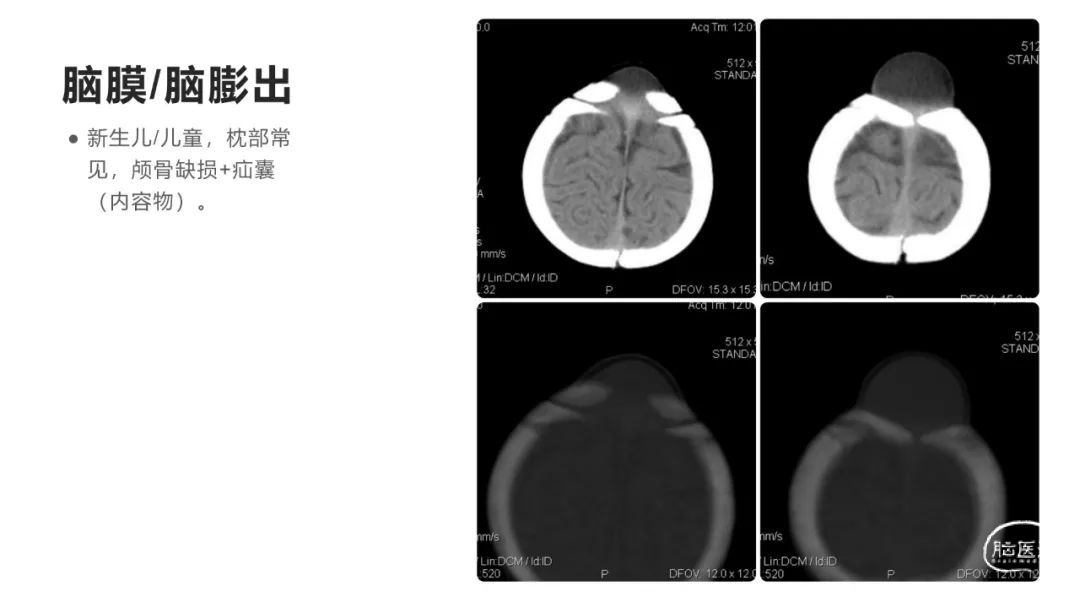

颅脑影像诊断基础知识讲座:颅骨病变